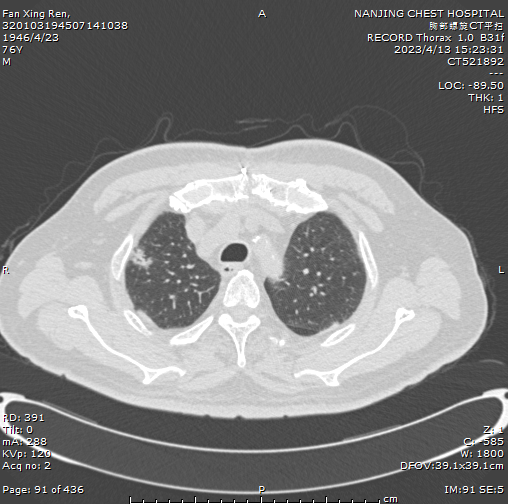

可是发现肺结节之后,如果患者不仅高龄还合并严重的基础疾病,例如:冠心病、糖尿病等还能不能手术呢?相信大多数患者和家人都有着这样的疑问或顾虑。 近日南京市胸科医院胸外科四病区就收治了这样一位患者。   患者范老先生,今年77岁,吸烟史40余年(3包/天),有糖尿病病史4年,2022年11月23日曾在我院体检发现肺结节,后因冠状动脉狭窄至行心脏搭桥手术,术后搭了4根桥,患者还患有腹主动脉瘤,放置了腹主动脉支架,恢复顺利。   2022年12月因为新冠肺炎疫情大面积爆发,阻碍了范老先生的求医之路。他向我们表示这段日子每天都度日如年,因为自己感染了新冠病毒,恢复了好久身体才得到康复。之后觉得一刻也不能再耽误。辗转多家大型综合性医院挂号问诊,后经过多方打听,于2023年4月13日在家人的陪伴下再次至我院,咨询了胸外科四病区专家——马国栋主任。 患者说自己是一位从军近30年的老军人,年轻的时候身体素质非常好,但是烟龄长,本身患有糖尿病、心脏又搭桥,顾虑重重总是担心自己肺质量差,影响手术效果和愈后,思虑再三最终决定到专业性最强的南京市胸科医院完成此次手术。 范老先生入院后,马国栋主任向范老先生及其家人分享了以往在我院类似成功手术病例给了病人极大的信心,解除了几个月焦虑紧张的情绪。并且针对范老先生疾病的特殊性,精心制定了一系列个体化的诊疗方案。 术前CT报告 在完善了相关术前检查、充分评估病情、排除手术禁忌。于2023年4月19日行胸腔镜肺叶部分切除+淋巴结清扫术,患者年纪大同时患有糖尿病及心脏病,在马主任及其团队医师的通力合作下,手术顺利完成,时长仅2小时,术中出血仅10ml。 术后病理报告 术后通过马主任团队医师们的精心诊治、病区护理团队悉心照顾之下,范老先生术后恢复良好,术后第3日拔除胸腔引流管,手术切口愈合佳,无红肿渗液。 人间最美四月天,最美不过夕阳红,在这个草长莺飞的春季,一位老军人诚挚的向马主任团队表示了感谢。 病区走廊里范老先生在护士的指导下做呼吸操、手部爬墙运动、肺部康复锻炼,忙得不亦乐乎,护士告诉老人不能太累,他笑呵呵的说:我是铁骨铮铮的军人,不知道累是什么......走廊里传来老人和护士爽朗的笑声,我们也发自内心的为老人在这么短时间内恢复这么快感到高兴。 有时是治愈,常常是帮助,总是去安慰,这是一句多么平凡的座右铭,细细品味,韵味十足,愿每个老年人都能度过一个安详平和有质量的老年时光。  患者经历